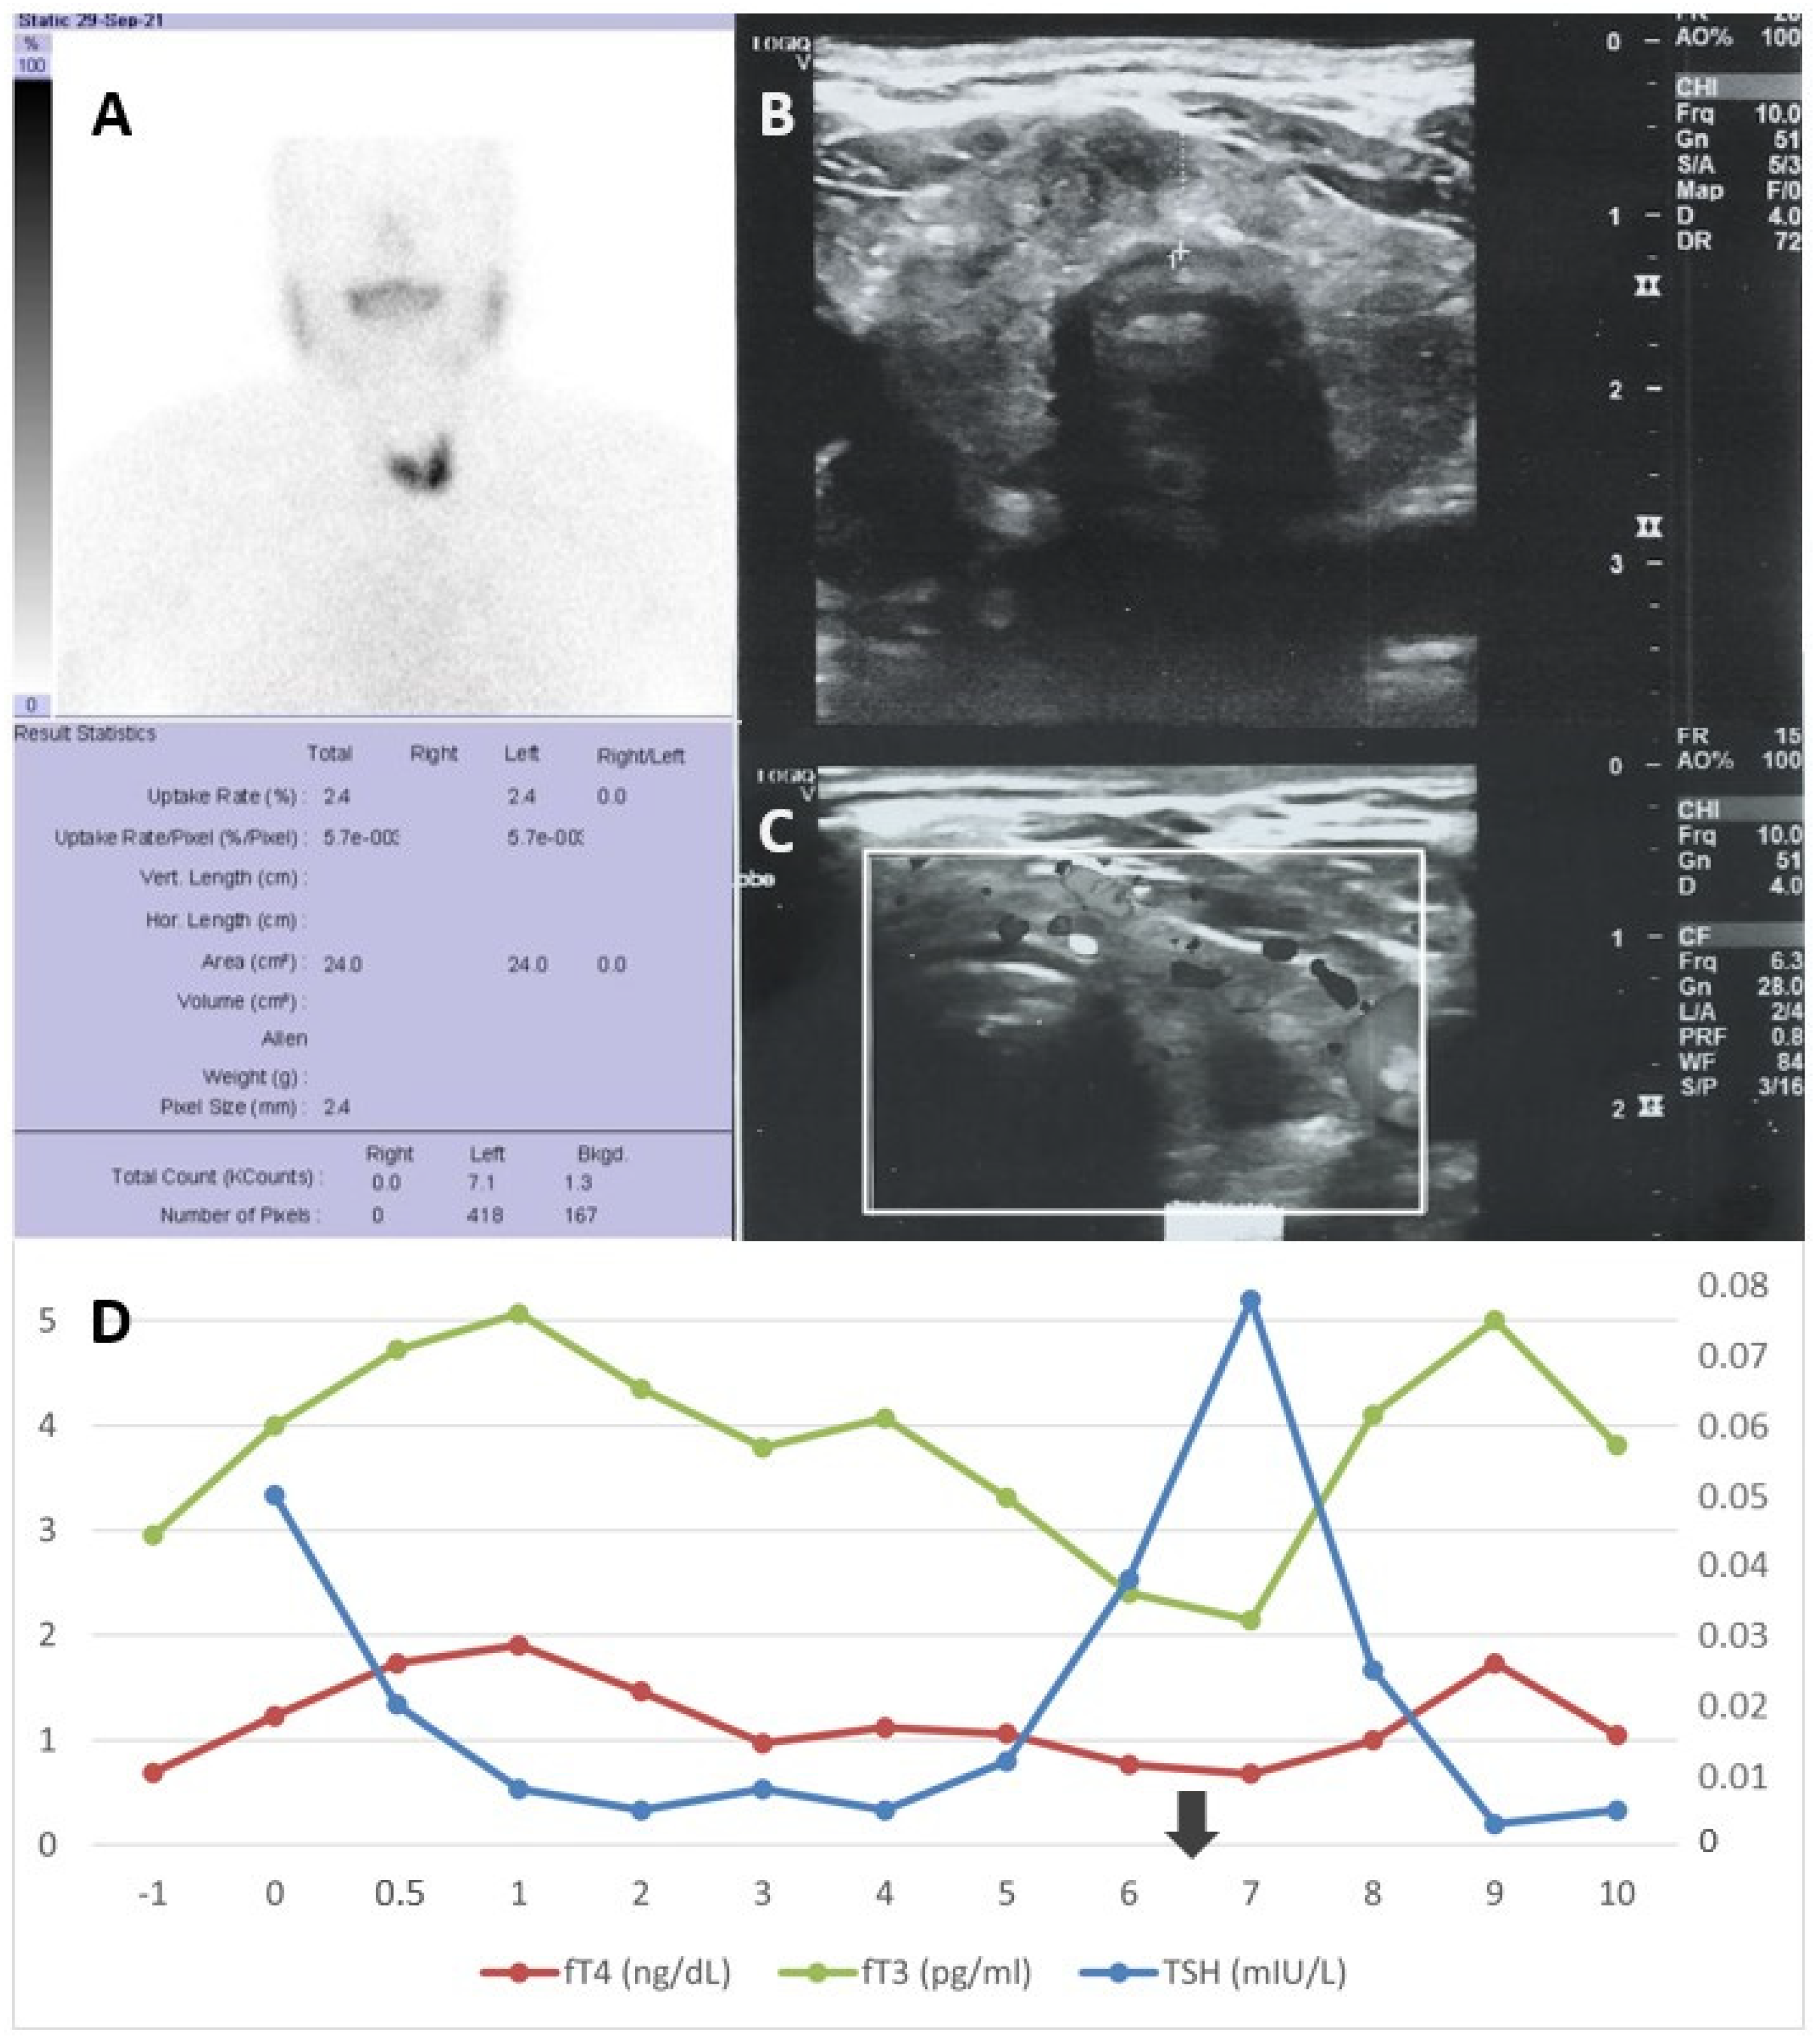

2.1. Case 1

2.2. Case 2